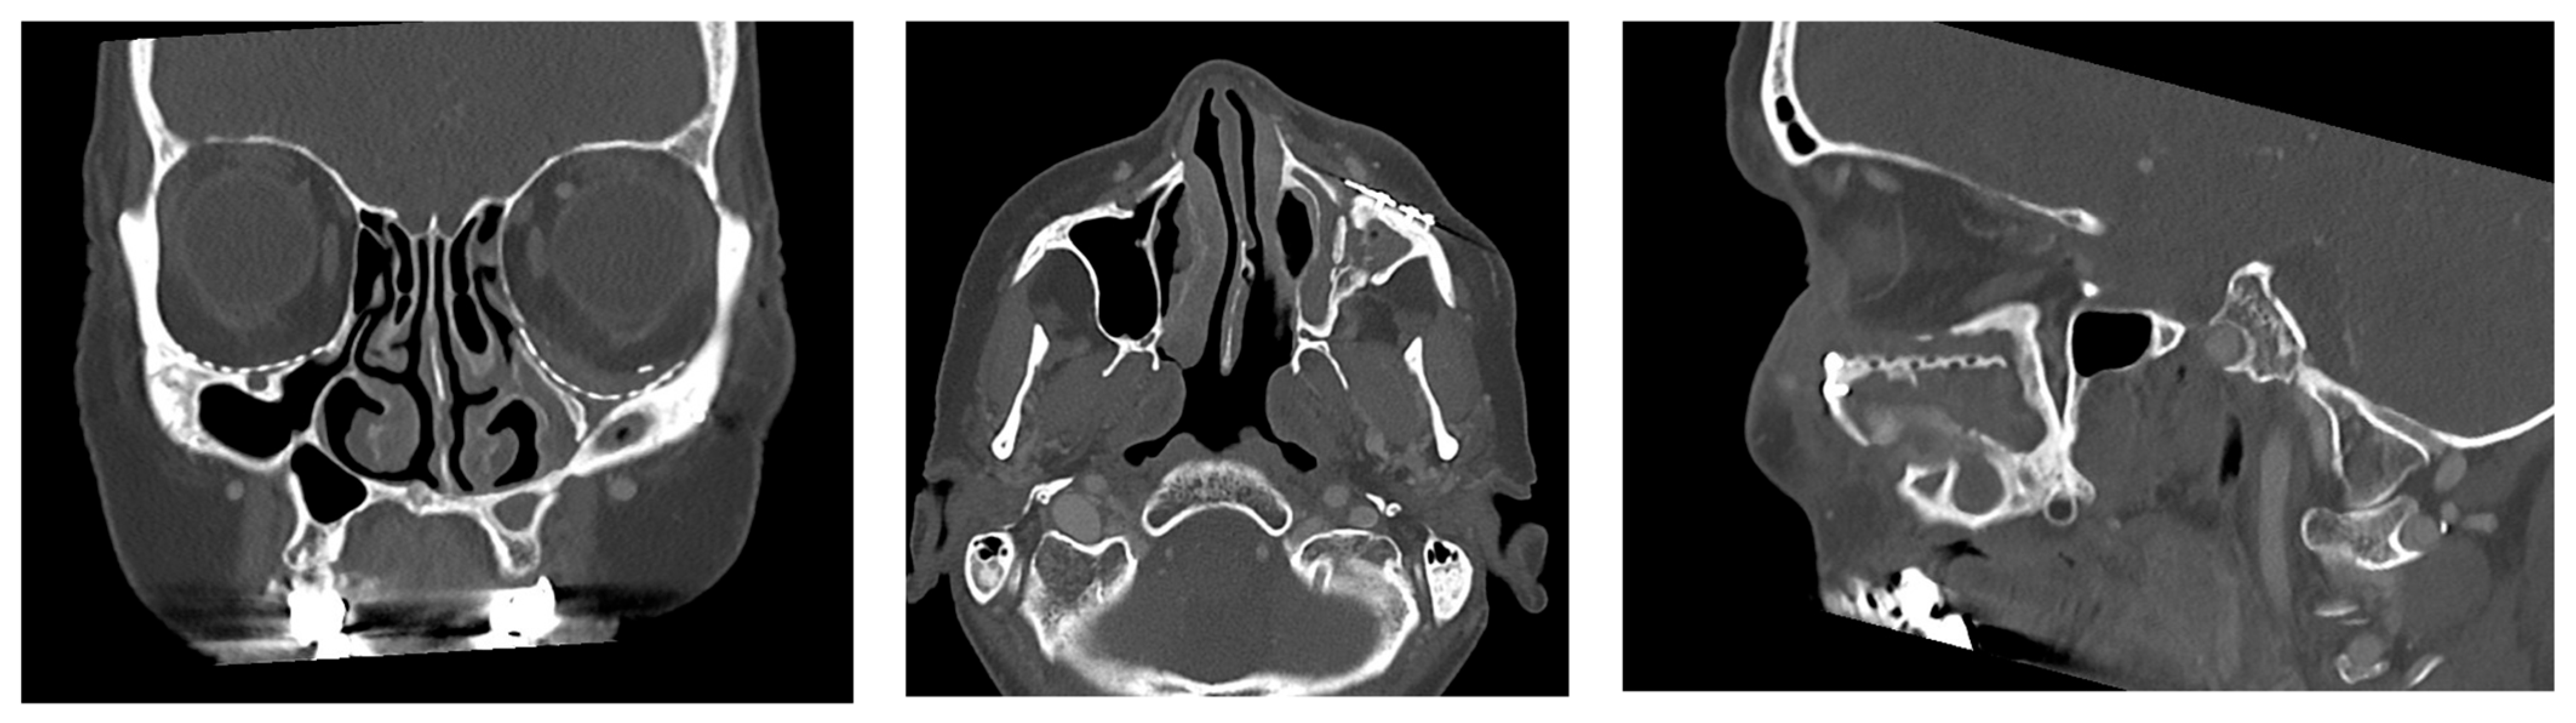

| 9 | February 2019 April 2021 (26 months) | Asymmetry, telecanthus on the right, scars in the nasal region | Yes | 5/5 | No | Ethmoidal | Yes |